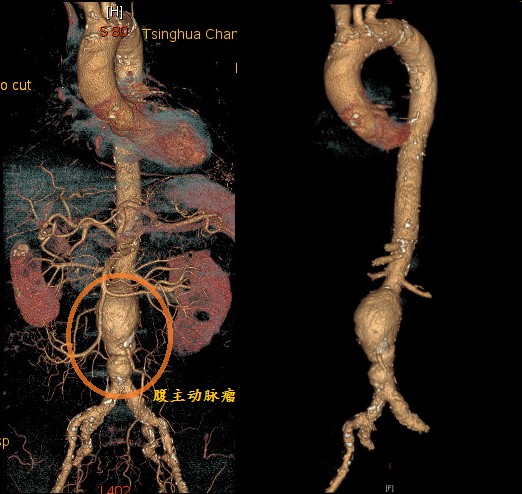

患者老杨今年95岁,戎马一生,刚获得了抗战70周年纪念章,与88岁的老伴相依相偎70余年。贴着老爷子的肚子,可以清楚地摸到一个搏动性包块,前来血管外科吴巍巍主任的门诊就诊,确诊是腹主动脉瘤,直径6cm。腹主动脉瘤是一颗风险极大的潜藏炸弹,腹腔内人体最粗的腹主动脉由于动脉壁硬化、高血压冲击扩张形成动脉瘤,就像一个吹大的“气球”,随时可能破裂导致大失血而死亡。著名的科学家爱因斯坦、李四光都因动脉瘤意外破裂死亡。

腹主动脉是主动脉在腹部的延续,主要负责腹腔内脏、腹壁和下肢的血液供应。当腹主动脉某段发生扩张,直径超过正常腹主动脉直径的1.5倍以上时,即发生了腹主动脉瘤。腹主动脉瘤实际上是一种因动脉血管壁退化变性而导致的动脉扩张性疾病,如同一个管道局部变薄鼓起了一个包,本身是一种良性疾病,而非通常意义上的“肿瘤”,但其对人体健康的威胁却绝不亚于任何一种恶性肿瘤。

大多数腹主动脉瘤患者在血管破裂前几乎没有任何症状,在这种情况下,早期诊断、尽早治疗就显得尤为重要了。临床用于血管疾病的检查方法很多。首先是彩色多普勒超声检查,无创、廉价、操作简便,不但能迅速发现腹主动脉瘤,还能提供许多重要瘤体信息,如动脉瘤直径、长度、硬化斑块大小、血栓情况等。其次是增强CT检查,静脉注射造影剂可增强显示血流、提供管壁信息,通过三维重建,立体化呈现血管病变。腹主动脉瘤患者多数有动脉粥样硬化,可已影响心、脑、肾、肺等各大重要脏器,所以需要评估全身情况,比如,心电图、超声心动图了解心脏功能、有无心肌缺血等。